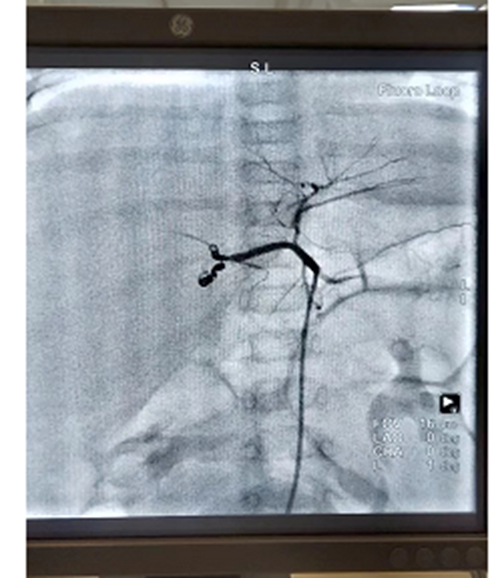

為讓患兒得到及時治療,破解治療難題,兒外中心邀請醫(yī)院副院長、心內(nèi)介入知名專家泮思林教授進(jìn)行會診,決定采用先通過高選擇性血管栓塞術(shù)介入,對腫瘤的供血血管進(jìn)行栓塞,使瘤體變小;再進(jìn)行外科手術(shù),完整切除腫瘤的治療方案。

患兒出生僅3個月,年齡小、體重輕,血管細(xì),介入手術(shù)難度極大。術(shù)前,各學(xué)科對各種可能出現(xiàn)的情況制定了應(yīng)急預(yù)案。術(shù)中,泮思林教授憑借精湛技術(shù)和豐富經(jīng)驗,順利將彈簧栓精準(zhǔn)送達(dá)擬定部位,肝母細(xì)胞瘤主要動脈血管被充分阻斷。術(shù)后,患兒腫瘤瘤體明顯縮小,大大減少了后續(xù)切除手術(shù)中瘤體出血風(fēng)險。